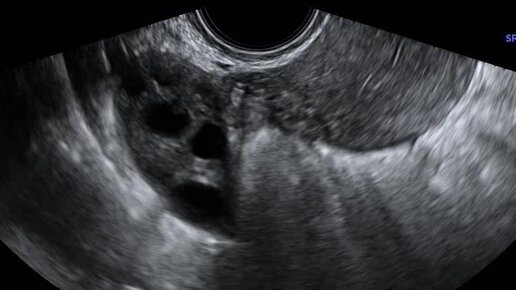

Видео: Поперечное сканирование матки. Правый яичник расположен у угла матки.

Ультразвуковые находки от врача УЗД Зорина Я.П.